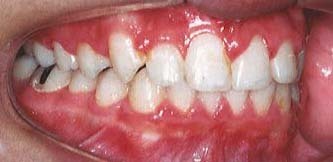

治療例2:叢生(でこぼこ)

いわゆる乱ぐい歯、凸凹の歯を叢生(そうせい)と呼んでいます。歯の大きさに対して受け皿である歯槽部の大きさが足りません。乳歯の早期喪失、舌癖(歯列に舌を押しつけて飲む癖など)等により歯列が広がらなかったためです。

治療には、歯列を広げて凸凹をとる場合と、抜歯により空隙を作る方法があります。下の例では、ヘッドギアを用いて奥歯を移動し、また歯列幅を広げることで抜歯をしないで治療しています。

治療前

※ あご(歯槽)が小さく、歯が並びきれていません。犬歯がはみ出しています(いわゆる八重歯)。

治療後

※ ヘッドギアで奥歯を移動し、また歯列を広げながら、かみ合わせを高くしています。抜歯をせずに凸凹がきれいになりました。

①主訴:歯のでこぼこを治したい。

②診断名:低位犬歯を伴う叢生

③年齢:16歳

④装置:マルチブラケット、ヘッドギア

⑤抜歯部位:なし

⑥治療期間:1年8か月

⑦治療費:79万円(メタルブラケット使用、総額)

⑧リスク、副作用:下記参照